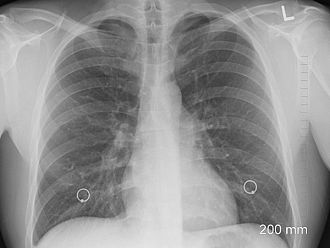

Ракът на белия дроб е най-тихо протичащият рак и се хваща в късен стадий. В България 5-годишната преживяемост е около 10%, подчерта Мира Ганова.

Тя допълни, че сред водещите рискови фактори са тютюнопушене, фамилна обремененост, излагане на вредни субстанции и газове – например радон. „Тютюнопушенето обаче е с най-голяма тежест като рисков фактор“, категорична беше Мира Ганова.

Има един златен стандарт за рак на белия дроб и това е нискодозова КТ. Какви са тези глупости и коледни инициативи на дигитални ентусиасти?!! Обърквате хората така! В настоящата ситуация и доста политици можете да объркате